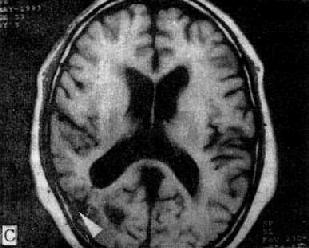

MRI 适宜于观察CT扫描为等密度的亚急性脑内血肿,已如前述。脑梗塞的发现MRI比CT扫描要早,一般起病后6小时MRI即可出现异常。脑干和小脑腔隙性梗塞灶的探测,MRI明显优于CT。脑梗塞灶在T1WI上呈低信号,在T2WI上呈高信号(图5-1-6C、D)。

图5-1-6 MRI扫描SE序列图像

在矢状面(A)和冠状面(B)T1WI可见垂体肿块向鞍上延伸,呈等信号区(→);在横断面T1WI(C)和T2WI(D)上分别可见左枕和右基底节区脑梗塞灶呈低和高信号区(→);在矢状面T1WI(E)和横断面T2WI(F)上,可见基底动脉瘤环形影,其内为低信号和高信号区,高信号区为瘤内血栓形成(→)